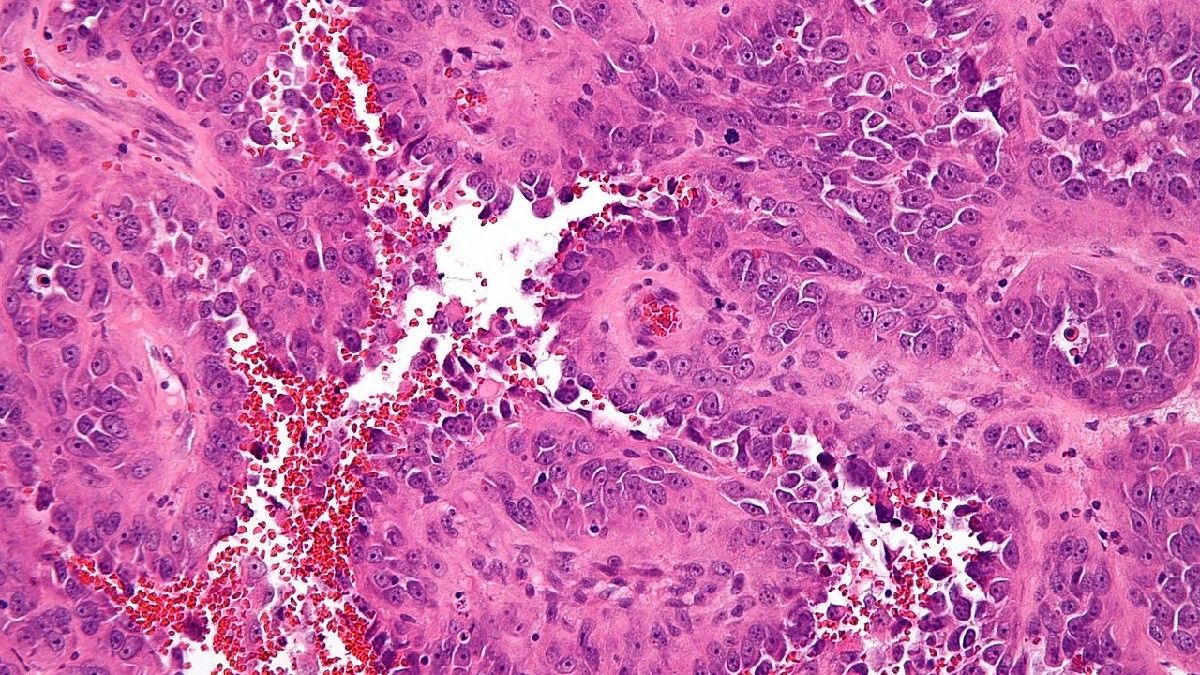

5. Angiosarcoma

Angiosarcoma merupakan jenis kanker payudara yang sangat langka. Dari sekian banyak pasien kanker payudara, hanya satu persen yang mengalami jenis kanker ini.

Kanker angiosarcoma muncul pada sel yang melapisi pembuluh darah atau getah bening payudara. Biasanya, jenis kanker ini terjadi karena paparan radiasi di bagian payudara.